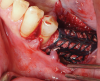

The patient received amoxicillin 500 mg 3 times a day for 10 days, starting the day before surgery.13,14 A full-thickness flap was elevated, extending from tooth No. 22 to at least one tooth mesial and distal to the mesh placement area (Figure 3). Although a vertical releasing incision was not necessary mesially, one can be made to allow sufficient tissue and ensure tension-free closure. It is important that the vertical incision does not end at the joint between the host bone and mesh. The periosteum in this case was left intact and no superficial release of the mylohyoid lingual was necessary.3,15,16

Fig 3. Premolar extracted and flap release.

Figure 3